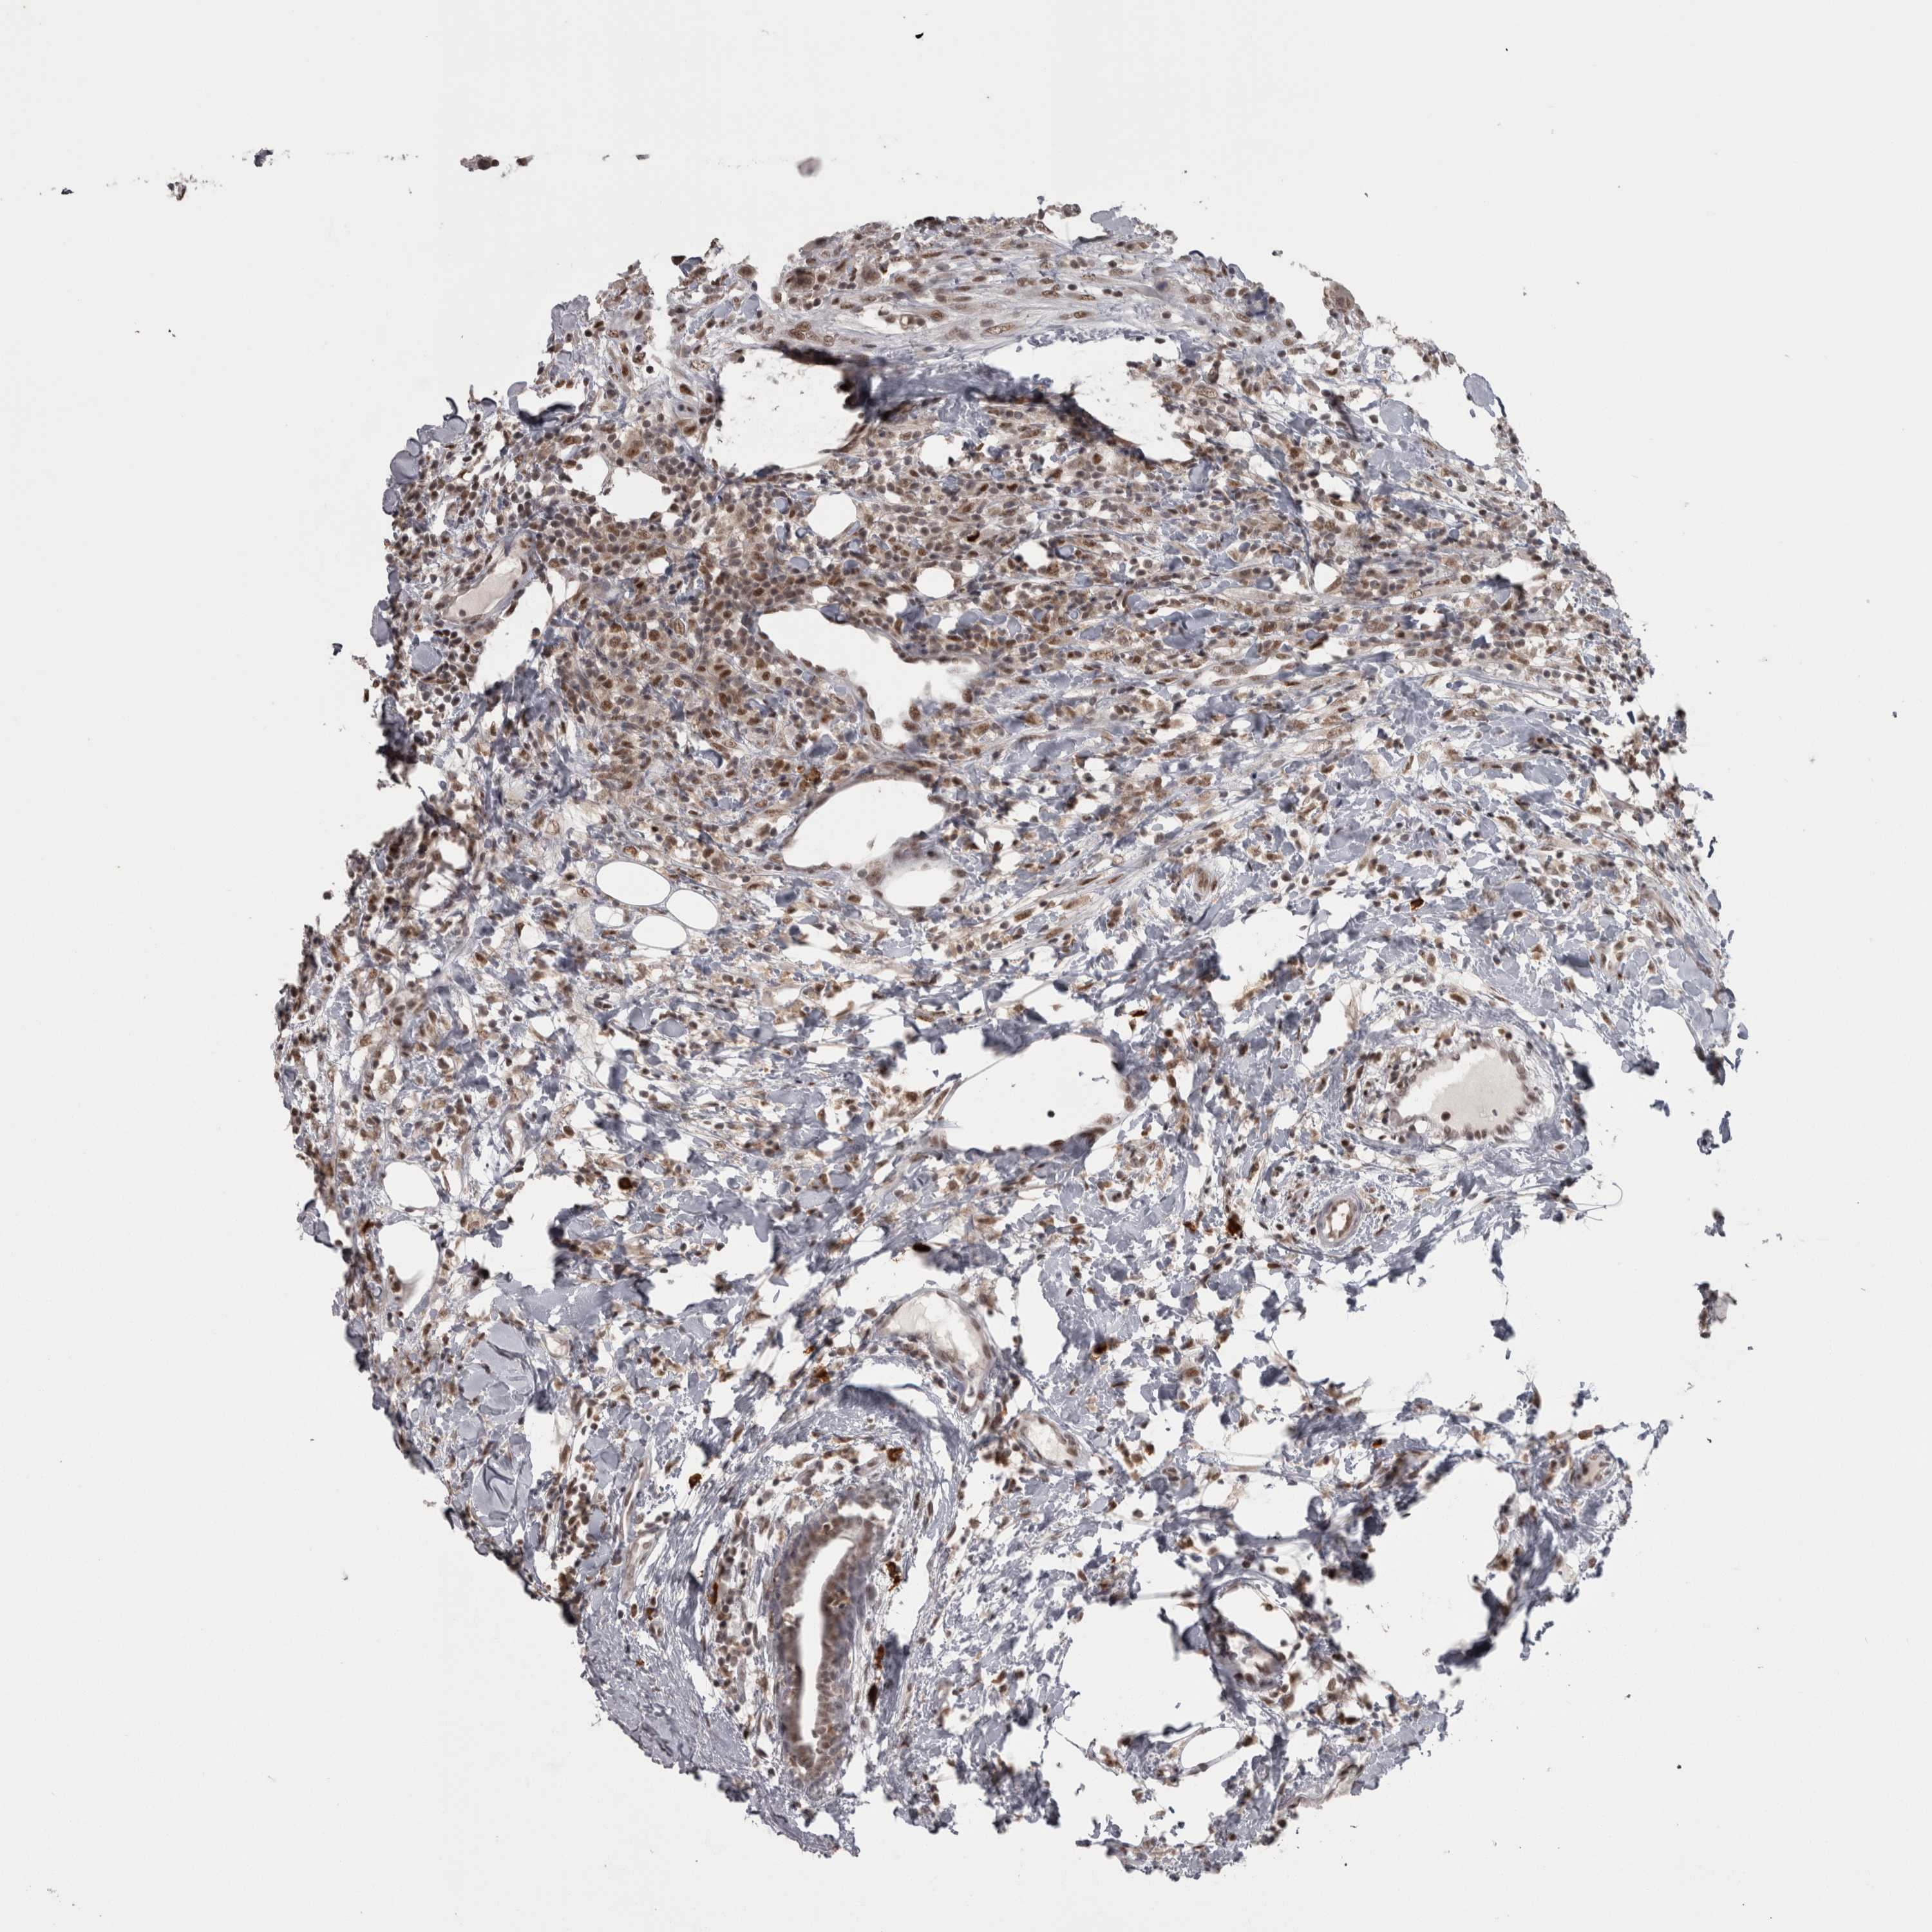

CANCER BREAST CANCER Show tissue menu

BRCA TCGA BRCA VALIDATION PROTEIN EXPRESSION